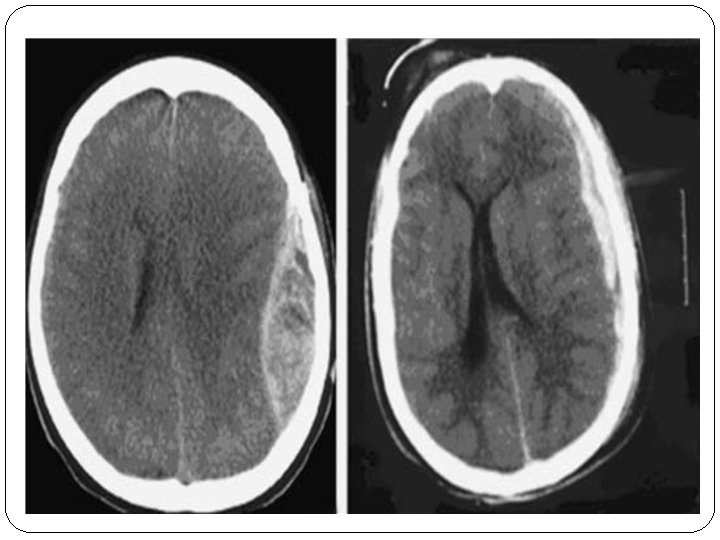

Hémorragie sous arachnoïdienne post traumatique

Hémorragie intra ventriculaire